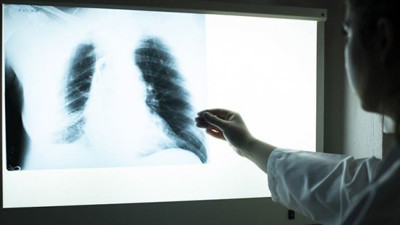

Genç doktor paylaştı ve uyardı: İşte korona virüs geçiren akciğer görüntüsü Acil hekimi olarak görev yapan 28 yaşındaki Dr. Fatih Cırıl, 1,5 ay önce koronavirüs’e yakalandı. Sigara dahi kullanmayan, hiçbir kronik hastalığı olmayan genç doktor, hastalık yüzünden on günde 7-8 kilo verdi, yoğun bakımın eşiğinden döndü.

Korona ciğerleri bu hale getiriyor: Siz hâlâ dışarıda gezin Radyoloji uzmanı Prof Dr Güner Sönmez, korona virüsün akciğerlerdeki etkilerini gözler önüne seren bir paylaşımda bulundu. Sönmez, salgına ilişkin takipçilerinin de sorularını yanıtladı.